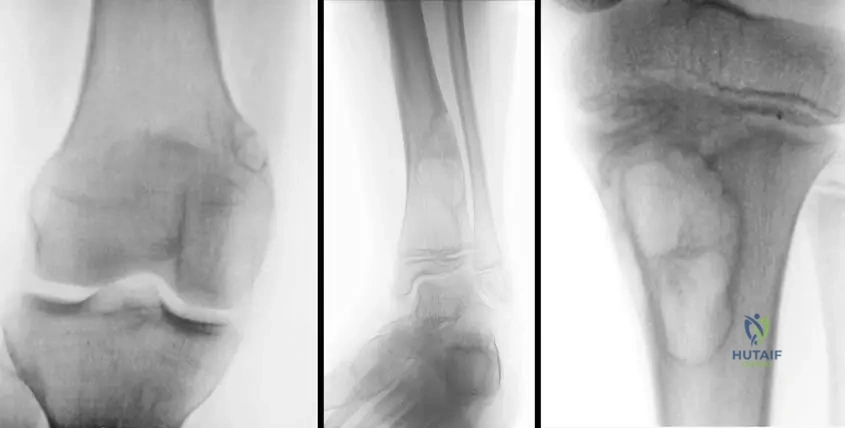

A 13-year-old male presents with an incidental finding of a nonossifying fibroma. The provided image, Fig. 11.16a, shows a characteristic location for these lesions. Which specific bone and region is depicted in Fig. 11.16a?

View Answer & Explanation

Correct Answer: C

Rationale: The image caption explicitly states, "Fig. 11.16 a–c These lesions are usually eccentric and metaphyseal, often occurring in the long bones of the lower extremity, including the distal femur (a) and distal (b) and proximal (c) tibia." Therefore, Fig. 11.16a depicts the distal femur.

Question 71

A 16-year-old female is diagnosed with an asymptomatic nonossifying fibroma. The provided image, Fig. 11.16b, illustrates another common location for these lesions. Which specific bone and region is depicted in Fig. 11.16b?

Correct Answer: B

Rationale: The image caption explicitly states, "Fig. 11.16 a–c These lesions are usually eccentric and metaphyseal, often occurring in the long bones of the lower extremity, including the distal femur (a) and distal (b) and proximal (c) tibia." Therefore, Fig. 11.16b depicts the distal tibia.

Question 72

A 10-year-old male presents with an incidental finding of a nonossifying fibroma. The provided image, Fig. 11.16c, demonstrates a third common location for these lesions. Which specific bone and region is depicted in Fig. 11.16c?

Rationale: The image caption explicitly states, "Fig. 11.16 a–c These lesions are usually eccentric and metaphyseal, often occurring in the long bones of the lower extremity, including the distal femur (a) and distal (b) and proximal (c) tibia." Therefore, Fig. 11.16c depicts the proximal tibia.